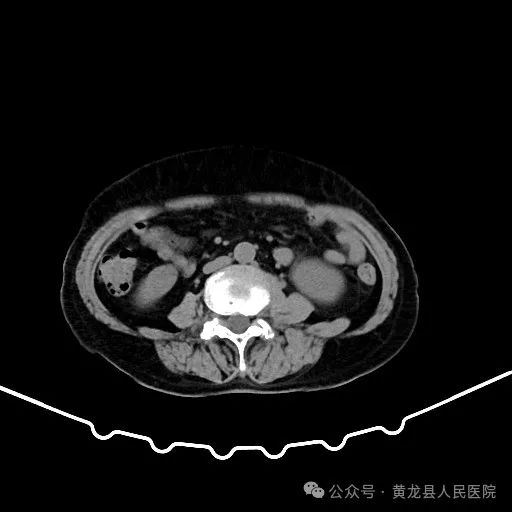

患者男性,70岁,因“发现右肾肿物1年余”收住于我院外科,经查体及相关检查后诊断为:右肾肿瘤。为尽早解除患者疾病困扰,方继荣主任迅速组织泌尿外科、手麻科、普外科等多学科进行会诊,对患者的病情进行了全面而深入的评估。最终确定详细周密手术方案,将患者病情及治疗方法告知患者及家属征得同意后,由我院泌尿外科刘涛主治医师实施手术。

双肾增强CT